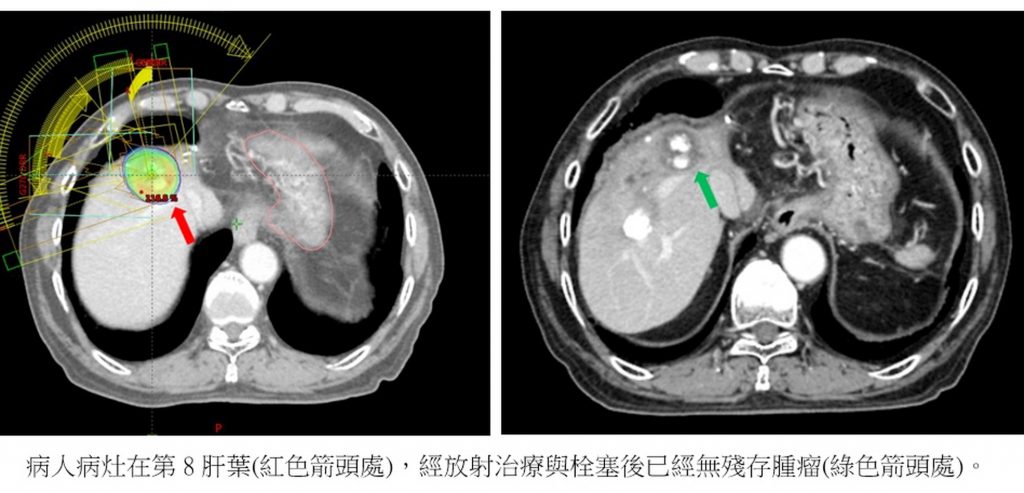

許維中表示,這位病人20年前檢查出罹患肝癌後,立刻手術切除部分肝葉,以為就此相安無事,沒想到3年後又發現1顆肝腫瘤,以放射治療精準撲殺後,5年後再度復發,治療後沒隔幾年又復發,前前後後總共做了5次放射治療和7次栓塞治療。病人面對治療時,總是樂觀地說:「我是肝癌的死對頭,它要我的命,我也要癌細胞的命!」

許維中強調,對肝癌一再復發的病人,最重要是在不同的治療方式中,儘量保護病人的肝臟機能,降低對肝臟的損傷,這樣量身打造的消滅腫瘤才有意義。以往病人多次重複進行栓塞治療,病人的肝功能可能會變差。因此,使用電燒或放射治療精準針對腫瘤的特定範圍進行撲殺,可以有效保護正常肝臟的機能。